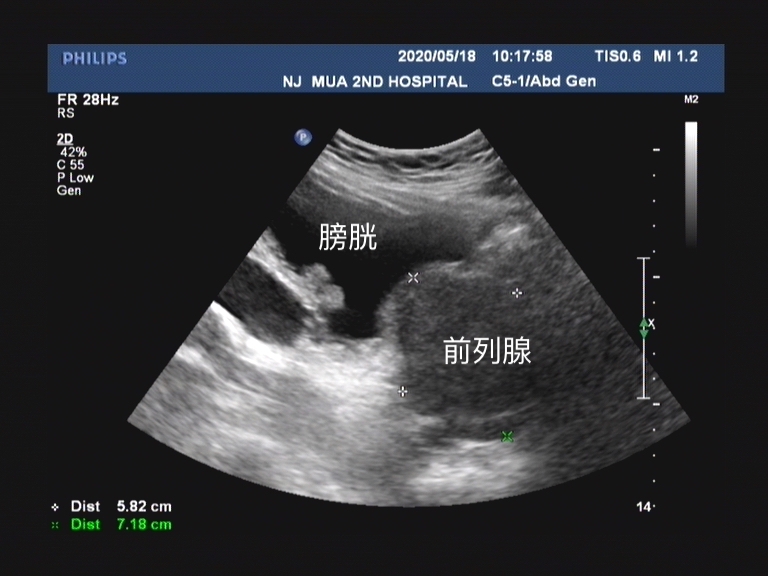

前列腺增生随着病程延长,慢慢的膀胱为了克服排尿的阻力,逼尿肌增强开始出现代偿性的肥大, 但这并不是真正的增强肌肉,而是平滑肌纤维增生 。慢慢的膀胱形态就开始出现了变化,增生的肌束纵横交错,成为粗大的网状结构。也就是彩超中经常能看到的一个描述,叫 膀胱小梁小室形成。

在这一过程中,膀胱内的压力开始增高, 当导致输尿管末端的活瓣作用丧失的时候,就会发现膀胱输尿管反流。就会逐步加重肾积水,慢慢的开始肾功能损害。